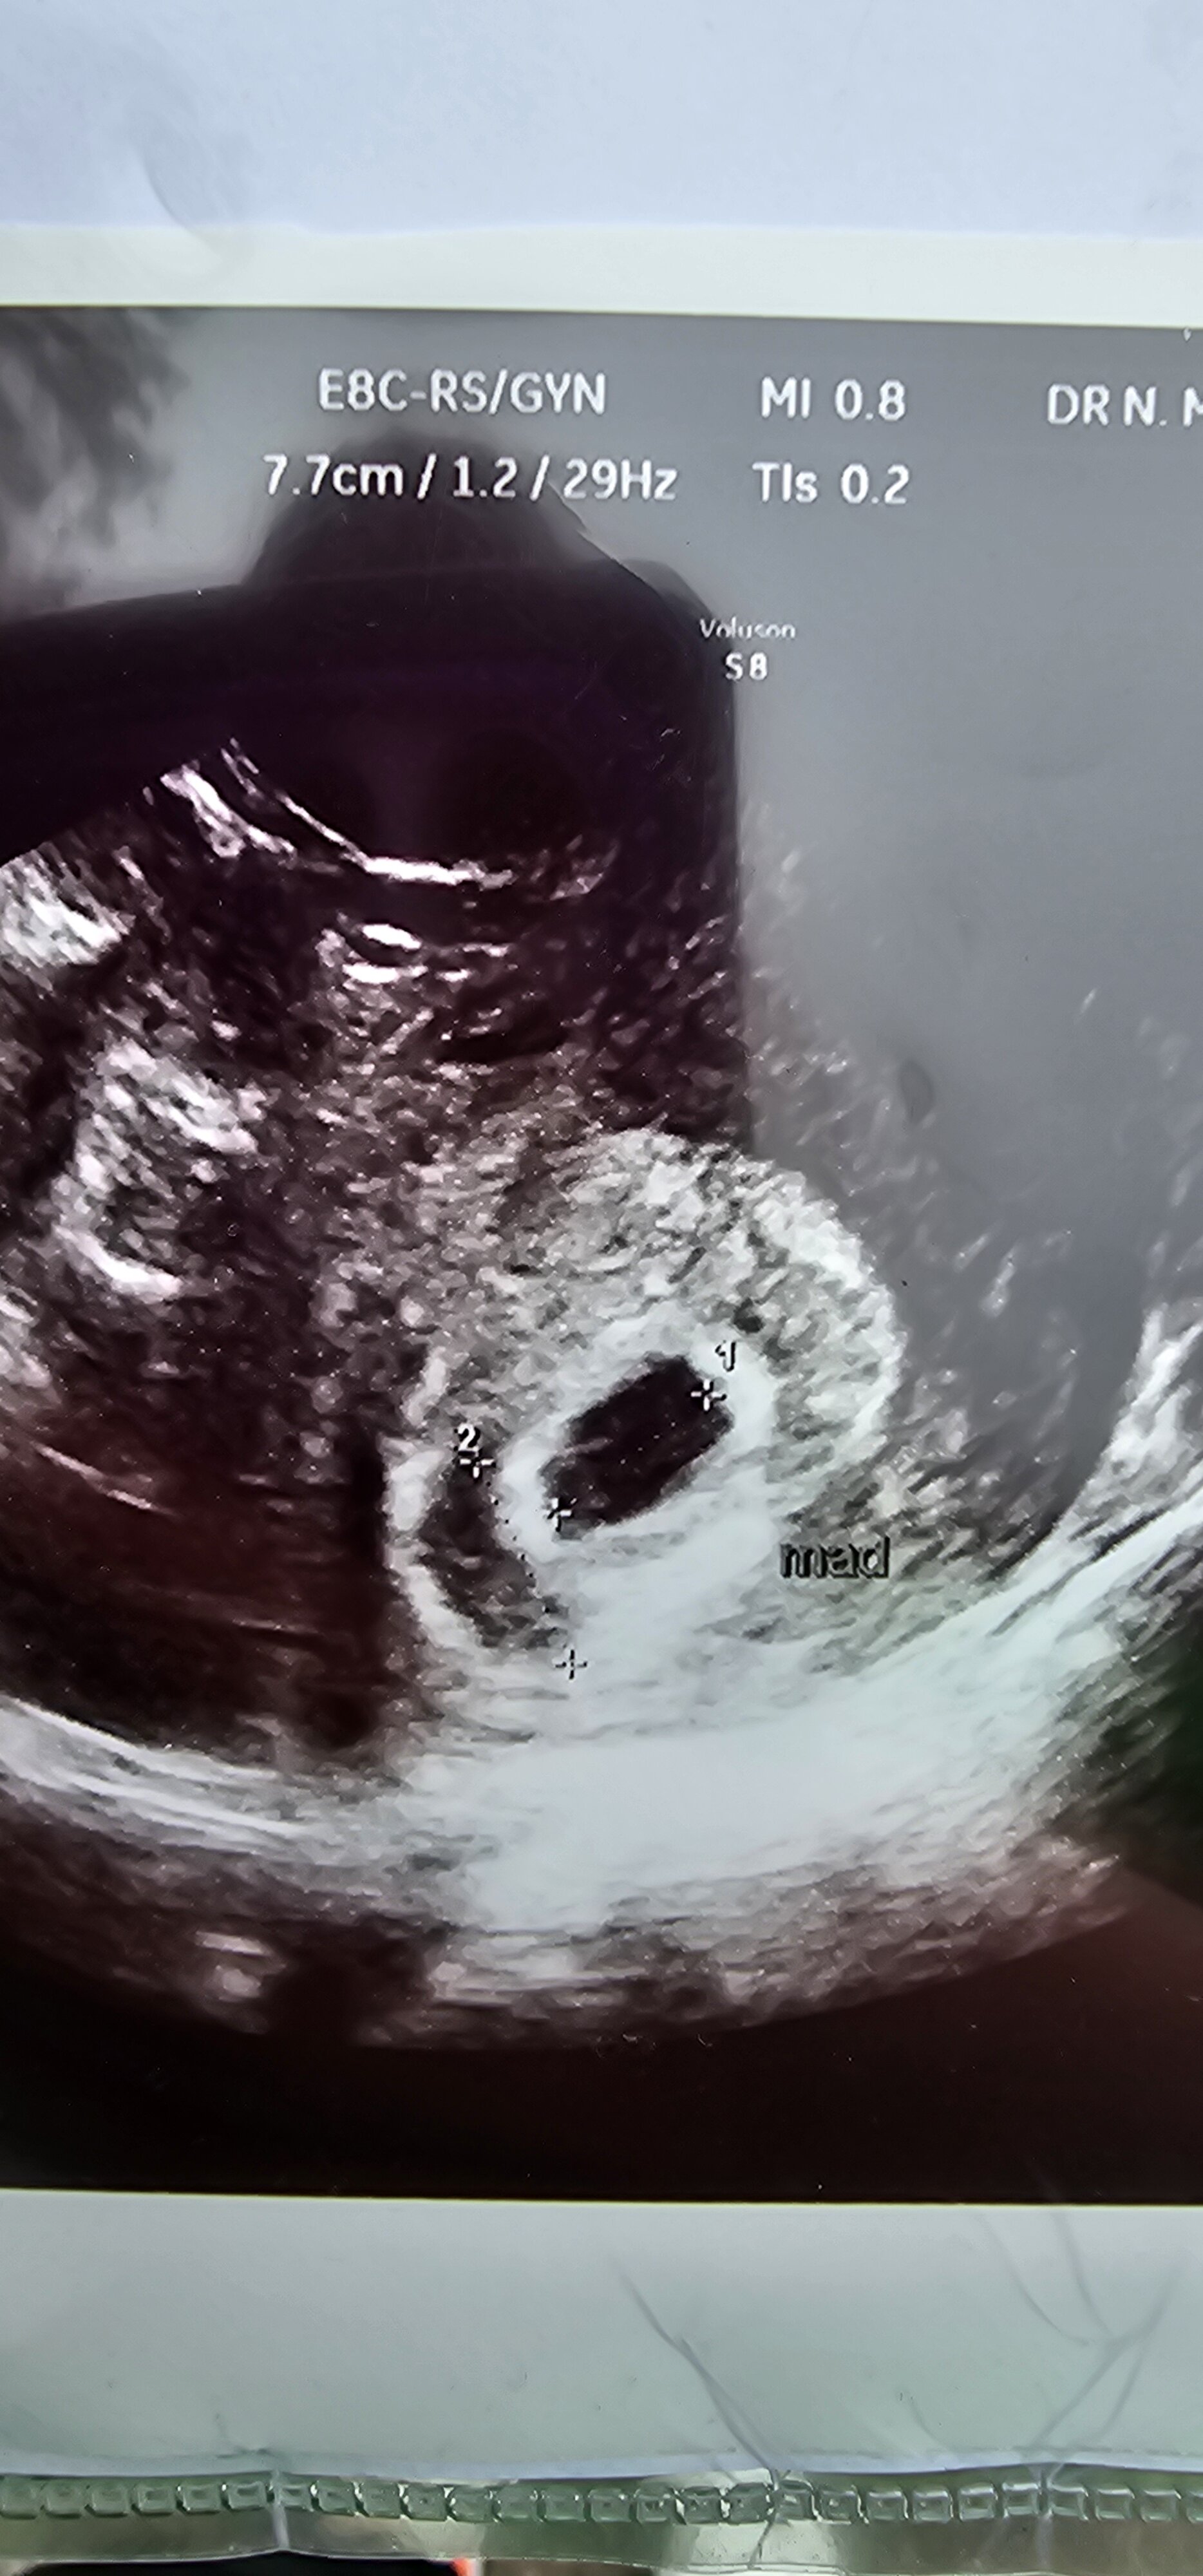

Hej. Byłam na wizycie. Widziałam swojego okruszka, termin mam na 30.11. 24. Prawie 0.9 cm czlowieczka ❤️ dzisiaj 6+6

• 20240412_141845.jpg

20240412_141845.jpg

1,2 MB · Wyświetleń: 120